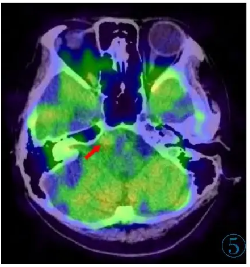

脑原发恶性黑色素瘤并发瘤卒中1例

病例

2025-10-09